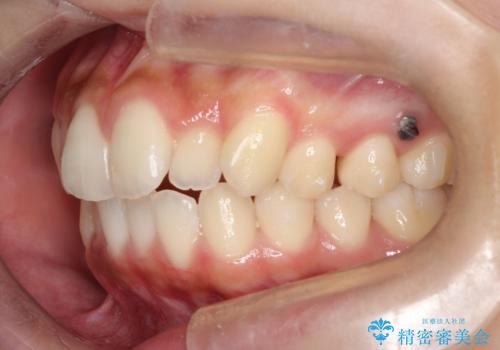

初診時の歯並びの状態としては、上下ともに全体に及ぶの中等度のがたつき(叢生)があり、全特に左上の前歯は1本だけ引っ込んでいる状態でした。

上の歯を後ろに送る方法として、歯茎に入れた小さなネジからゴムかけをして歯列全体を後ろに引っ張りました。